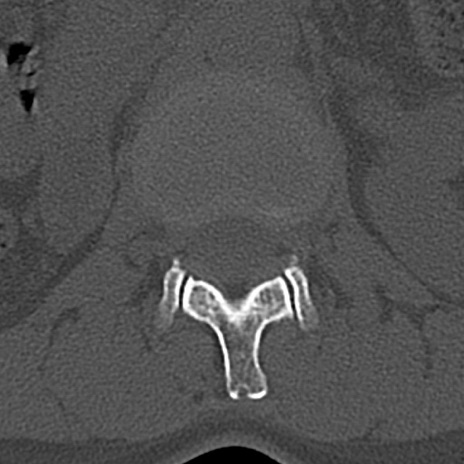

【整形】TIPS症例4 腰椎CT(横断像)

腰椎CT

横断像と矢状断像